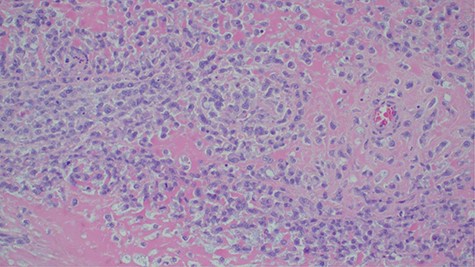

Laboratory investigations revealed a low platelet level of 53 per microliter and hemoglobin level of 10.7 g/dl. Renal profile, white blood count and serum electrolytes were within normal range. Computed tomography intravenous urogram revealed a large heterogeneous mass, measuring 5.5 × 4.5 cm at the right superolateral aspect of the urinary bladder with ipsilateral hydronephrosis and hydroureter. Bone scan study was unremarkable. Urothelial cell carcinoma of the urinary bladder was clinically suggested as the most likely differential diagnosis. Cystoscopy was done under spinal anesthesia, which revealed a solid mass with areas of necrosis at the anterior bladder wall. The biopsy was taken whose histological evaluation revealed a high-grade malignant mesenchymal tumor made up of oval or spindle cells with osteoid formation in many areas of the lesion (Fig. 1). No definite carcinomatous component was appreciated. The tumor was strongly positive for vimentin immunohistochemistry staining (Fig. 2) and negative for cytokeratin 20. Calcified schistosomal ova were also seen (Fig. 3).

Strongly positive for vimentin immunohistochemistry staining of the tumor cells (×100).